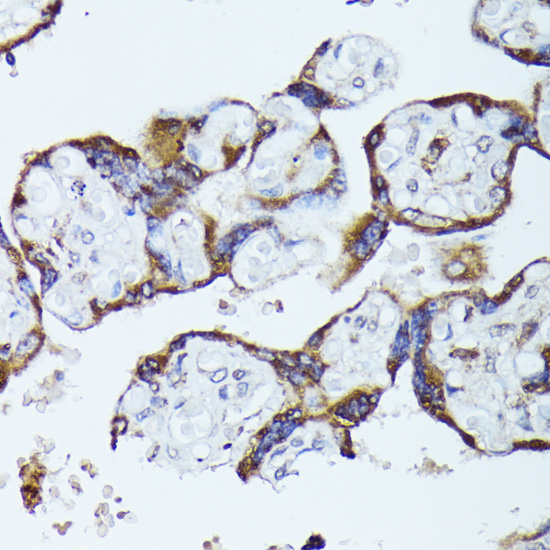

Immunohistochemistry of paraffin-embedded human placenta using TBCB at dilution of 1:100 (40x lens).

,